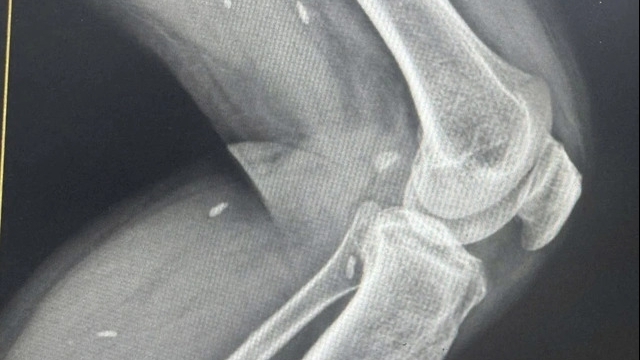

![]() |

| Nhiều loại rác thải công nghiệp bị vứt bừa bãi ngoài môi trường |